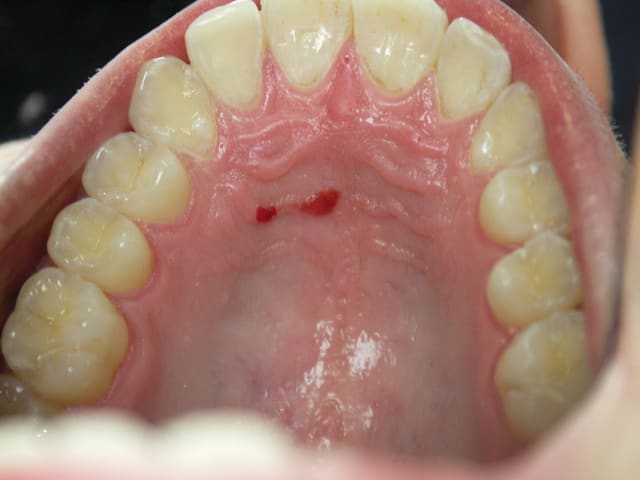

Besoin d'un avis sur cette lésion au palais d'un patient de 25 ans , sans problèmes de santé.

En passant le dos de la sonde dessus, pas de décoloration ni de reliefs , absence de douleurs .

Le patient n'avait pas connaissance de cette lésion à cet endroit.

Fumeur depuis 6/7 ans , 15 cigarettes par jour.

on dirait de petits angiomes..

idem, petits angiomes je pense

Faut attendre 1 semaine pour moi c'est juste une blessure.

Angiome=> Disparait a la pression

Kaposi => Disparait PAS a la pression.

Tumeur maligne => Ca n'a pas vraiment la gueule. Quoi que...

Purpura/petechie => Tres tres peu probable.

Oh ben, les erythroplasies sont fréquemment associées au carcinome epidermoide.

Est ce qu'il y a un aspect "velouté" ? On dirait que non

Le plus probable reste la blessure qui va disparaître sous peu.